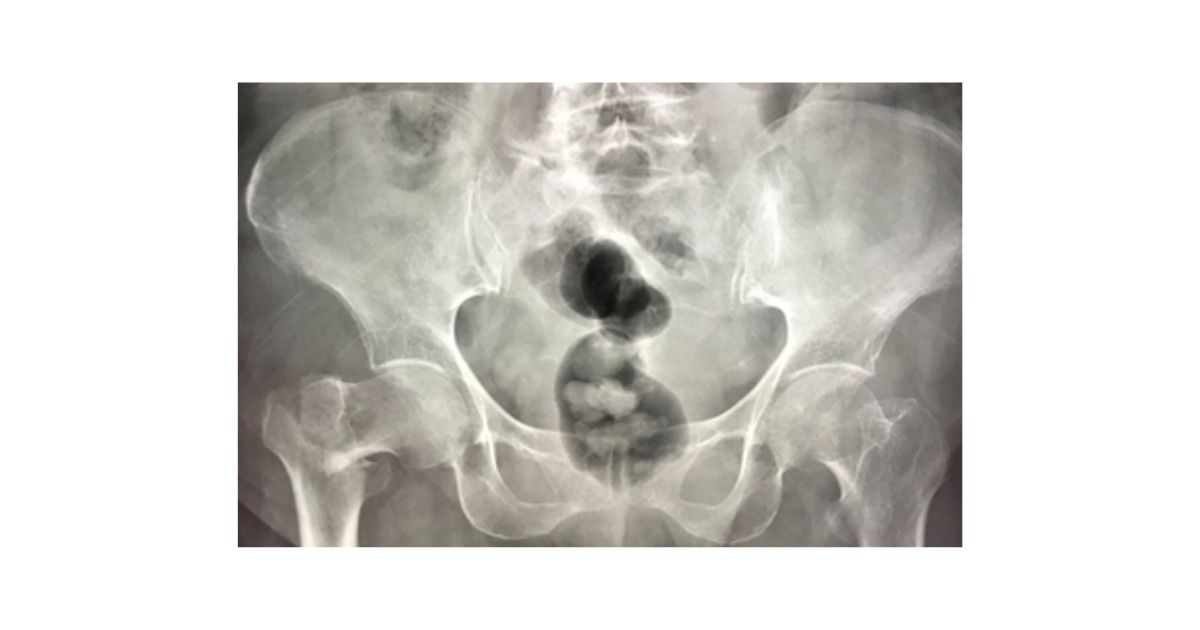

ภาพ X-ray แสดงการหักของกระดูกสะโพกข้างขวา

อาการที่ควรจะสงสัยและพามาพบแพทย์ ได้แก่ อาการปวดบริเวณรอบสะโพก ไม่สามารถขยับ หรือลงน้ำหนักที่ขาข้างนั้น ขาข้างที่เจ็บอาจจะดูสั้นกว่าอีกข้าง  นอกจากนี้ในรายที่เป็นกระดูกหักแบบไม่มีการเลื่อน อาการปวดจะไม่มาก และอาจลงน้ำหนักเดินได้ แต่หากปล่อยทิ้งไว้โดยไม่ได้รับการรักษาจะทำให้อาการบาดเจ็บเป็นมากขึ้นได้ จึงควรมาพบแพทย์เพื่อตรวจเพิ่มเติม โดยแพทย์จะทำการซักประวัติ ตรวจร่างกาย และทำการ X ray เพื่อยืนยันการวินิจฉัย